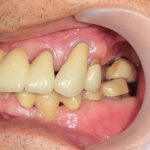

銀色のブリッジをジルコニアで自然に